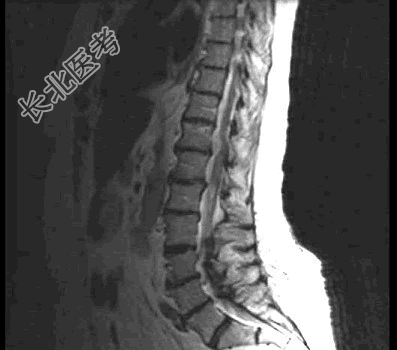

- 单项选择题患者,女, 68岁,头部剧痛伴左上肢无力半月余, 近两天发展为双下肢截瘫,请结合影像学检查, 选出最可能的诊断 ( )